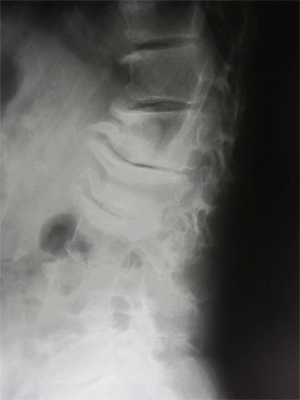

• 圧迫骨折

圧迫骨折は上下方向の力と前屈によって起こり骨粗しょう症の方はクシャミや腰を捻った、尻もちをついたなどの日常動作でも容易に圧迫骨折することがあります。

好発部位は胸から腰にかけての所(第11胸椎~第2腰痛の胸腰椎移行部)です。